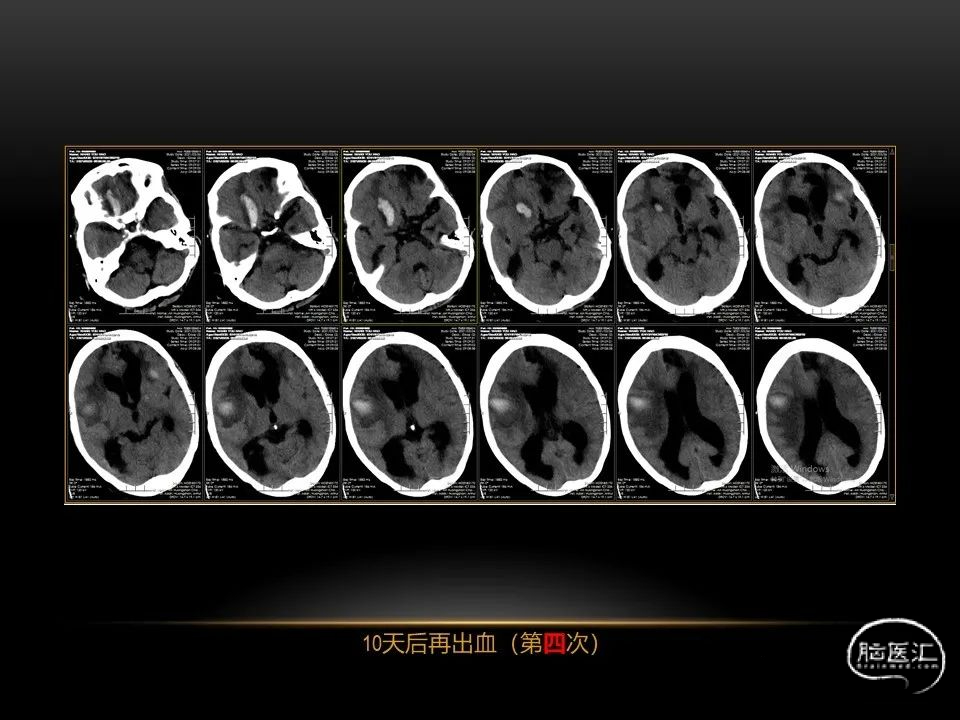

自发性脑出血临床上很常见,不同原因有特征性的出血部位。例如:基底节出血和丘脑出血大多是高血压性脑出血;脑叶出血,特别是多次复发的脑叶出血多见于老年人的脑血管淀粉样变。